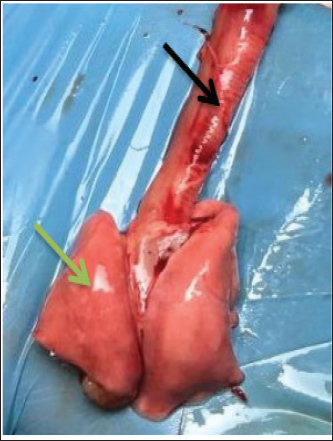

Fig. 3. Ventral view of lung for control group show (black arrow) trachea (green arrow) right lung.

Fig. 6. Group of infected rabbits lung (A) Bronchiols show emphysema aggregation of lymphocytic cell (black arrow)( B) show emphysema structure atelectasis (black arrow) H&E stain 400X and lung H&E stain 200X. Gross examination of sacrificed animals (group of infected rabbits) showed hemorrhage in the upper respiratory tract (Fig. 3). The trachea exhibited a semi-circular hyaline cartilage structure (Fig. 4), and the bronchi branched into left and right bronchioles, consistent with typical mammalian respiratory anatomy. Normal histological details of trachea of control group• Tunica mucosa • Tunica submucosa • Tunica adventitia • C-shaped hyaline cartilage (Fig. 5A) • score lesion of Pathological Changes • Emphysema was observed in 3 out of 5 cases (60%) (Fig. 4). • No pathological changes were seen in 2 cases (40%). • Vascular changes, including congestion, thrombosis, and alveolar hemorrhage, were noted in 10% of affected cases. Comparative morphologyLight microscopy analysis confirmed Gram-negative rods for Raoultella planticola. However, differentiation from Klebsiella spp. was challenging due to morphological similarities (Fig. 2A and B). The histological findings of emphysema and atelectasis align with Blagojević et al. (2018), who described similar structural changes in respiratory infections. The observed hemorrhage and vascular congestion support Castro et al. (2001), who linked these changes to bacterial-induced trauma. The 60% incidence of emphysema suggests that Raoultella planticola primarily induces chronic obstructive pulmonary disease (COPD)-like lesions, differing from Sarhad (2011), who reported fibrinous pleuropneumonia as the dominant pathology. This discrepancy may stem from differences in infection routes or host susceptibility. The short respiratory passage and direct bronchial branching in rabbits (Abdelsalam and Al Sadrani, 2015) likely contribute to higher lung infection rates. Additionally, the similarity between Raoultella and Klebsiella (Alampoondi Venkataramanan et al., 2021) complicates microscopic differentiation, necessitating advanced diagnostic methods like Vitek2.Contrary to Vinshia, J. J., (2024), this study found no fibrinous bronchopneumonia, instead emphasizing edema and congestion (Das and Bhagman, 1997). The reclassification of Raoultella from Klebsiella prior to 2001 further underscores the need for precise microbiological identification (Fig. 8). This study highlights Raoultella planticola's potential to cause respiratory pathology, warranting further investigation into its zoonotic risks.